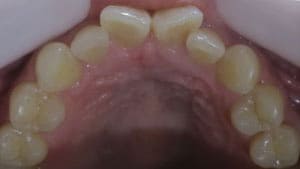

● 先天性の萌出方向異常を部分矯正で治療

藤沢デンタルオフィスの虫歯や破折で先天性の萌出方向異常を部分矯正で治療

04

05

06